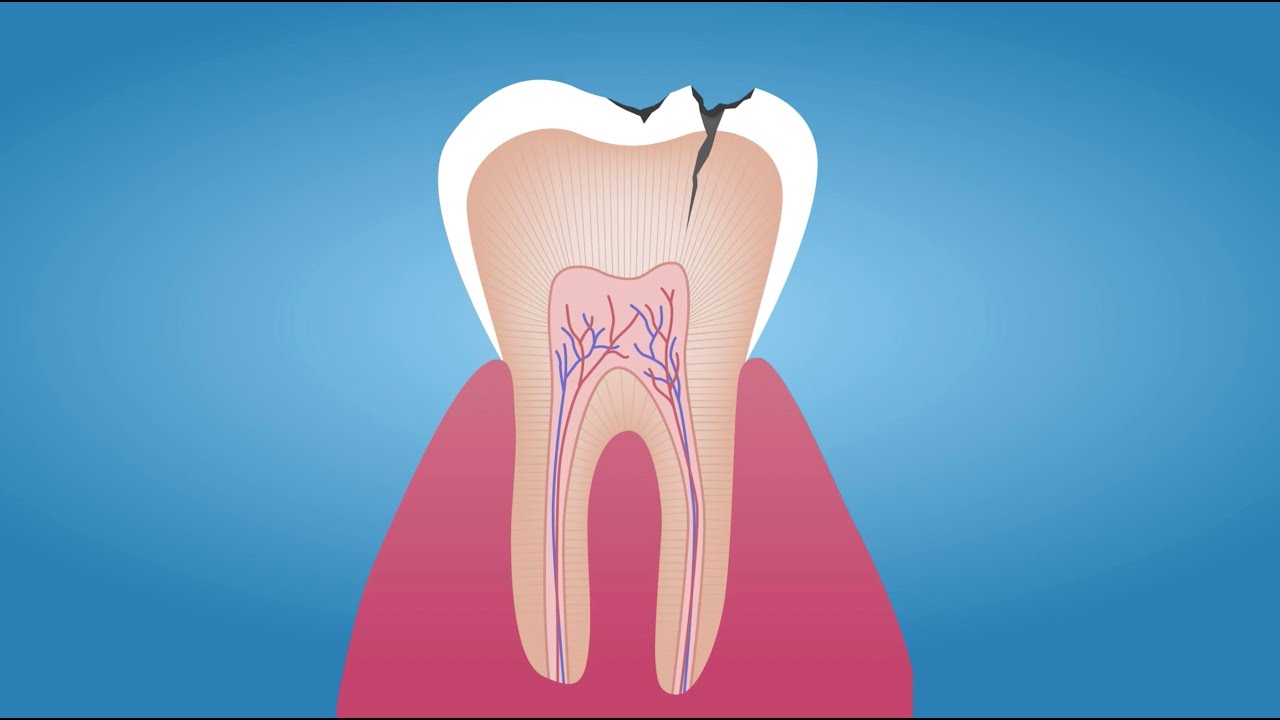

🦷 What Is a Cavity? What Causes Rotten Teeth?

What are Dead Teeth?

A Complete guide to rotten teeth, causes and treatment options